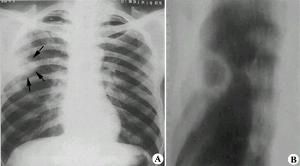

慢性肺炎的特點是周期性的復發和惡化,呈波浪型經過。由於病變的時期、年齡和個體的不同,症狀多種多樣。在靜止期體溫正常,無明顯體徵,幾乎沒有咳嗽,但在跑步和上樓時容易氣喘。在惡化期常伴有肺功能不全,出現發紺和呼吸困難,並由於肺活量和呼吸儲備減少及屏氣時間縮短等,引起過度通氣的外呼吸功能障礙。惡化後好轉很緩慢,經常咳痰,甚至出現面部浮腫、發紺、胸廓變形和杵狀指、趾。由於肺氣腫、肺功能不全而引起肺循環阻力增高,肺動脈壓力增高,右心負擔加重,可在半年至兩年內發生肺原性心臟病。還可能有肝功能障礙。白細胞增加,血沉中度增快。 X線胸片顯示在兩肺中下野及肺門區肺紋理可呈蜂窩狀,出現小泡性肺氣腫,同時還可伴有實質性炎症病灶。兩側肺門陰影可見對稱性增大。隨病變的發展還可發生支氣管擴張、右心室肥大及肺動脈段突出等肺原性心臟病的X線徵象。有肺原性心臟病時,心電圖表現順鐘向轉位,P波高而尖,QRS綜合波多數出現右心室肥厚圖型等改變。